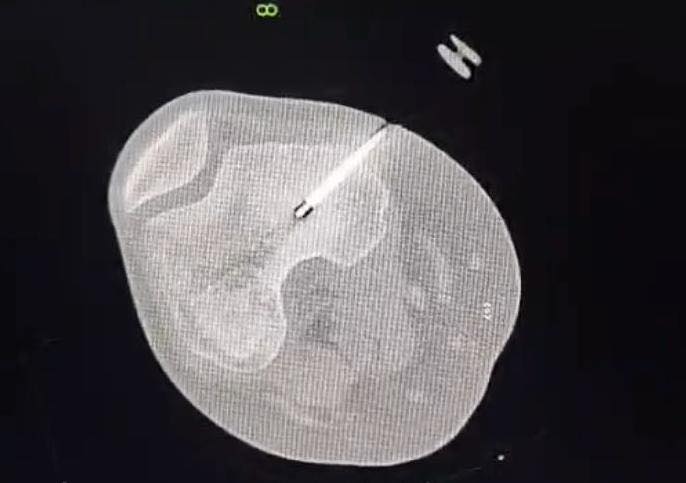

اجرى الكادر الطبي في مستشفى الأميرة بسمة عملية نوعية دقيقة لعلاج ورم عظمي حميد من نوع (Osteoid Osteoma) باستخدام تقنية الكي بالتردد الحراري (Radiofrequency Ablation) الموجهة بالأشعة المقطعية.

وتم إجراء هذا التدخل بنجاح من قبل الدكتور محمد نصر نزال والدكتور عثمان أبو قران أخصائيي الأشعة التداخلية وقسطرة الأوعية الدموية وبإشراف ومتابعة الدكتور عمر سميرات (أخصائي عظام الأطفال).

وبين الفريق الطبي أن خصوصية هذه الحالة تكمن في عمر المريضة (14 عاماً) حيث استقر الورم مباشرة على صفيحة النمو (Growth Plate) في عظم الفخذ البعيد. وتعتبر هذه المنطقة من الحساسية بمكان إذ ان أي خطأ قد يؤثر على النمو المستقبلي للعظم ما جعل استخدام تقنية الكي الحراري تحديا كبيرا يتطلب دقة فائقة لتجنب إلحاق أي ضرر حراري بالأنسجة المحيطة.

وبحسب بيان للمستشفى، تكللت العملية بالنجاح ، وتماثلت المريضة للشفاء واختفت آلامها الشديدة فور انتهاء الإجراء وهو ما يثبت فعالية العلاجات الحديثة "قليلة التداخل" في التعامل مع أعقد الحالات الطبية.